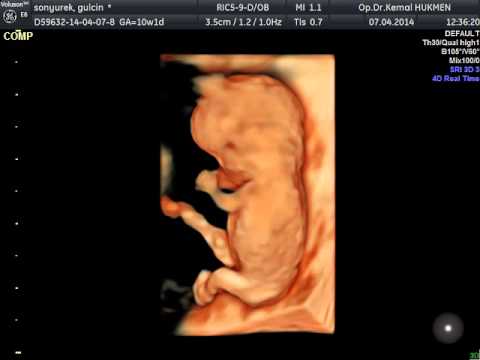

Kemal hükmen kadın hastalıkları doğum uzmanı hd live 3d 4d ultrason gebeli̇k taki̇bi̇ bebek sahi̇bi̇ olamama kizlik zari tami̇ri̇.